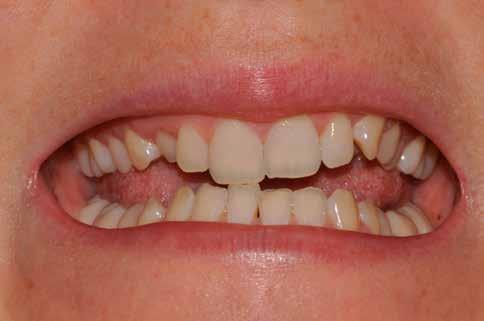

Egy 34 éves páciens esztétikai problémával érkezett. A természetesen keskeny metszőfogak miatt kisebb diasztémák és fekete háromszögek voltak láthatók a front régióban. A rések korábban kompozittal történő zárása már megtörtént, azonban az eredmény nem felelt meg az elvárásoknak (1. ábra). A fekete háromszögek továbbra is láthatóak voltak, és a kompozitanyag jól kivehetően helyezkedett el a fogak felszínén. A 11-es és 21-es fogak szélessége között aszimmetria mutatkozott, a korábbi restaurációk nehezen tisztíthatók voltak, és gyorsan elszíneződtek (2. ábra). A frontfogak palatinális felszínén retenciós drót volt rögzítve, a 11-es és 21-es fogak pedig kompozittal történő sínnel voltak összekötve (3. ábra). Bármilyen további kezelés során a retenciós drót eltávolítása szükséges, mivel az akadályozza a megfelelő approximális restaurációk kivitelezését. Az első konzultáció során teljes fotódokumentáció készült. Egy gyors kompozit mock-up segítségével bemutatásra kerültek a lehetséges esztétikai eredmények. A kezelési terv elfogadását követően időpont egyeztetésre került sor a beavatkozás elvégzésére.

1. ábra: A mosolyról készült fénykép a kezdeti vizsgálat során.